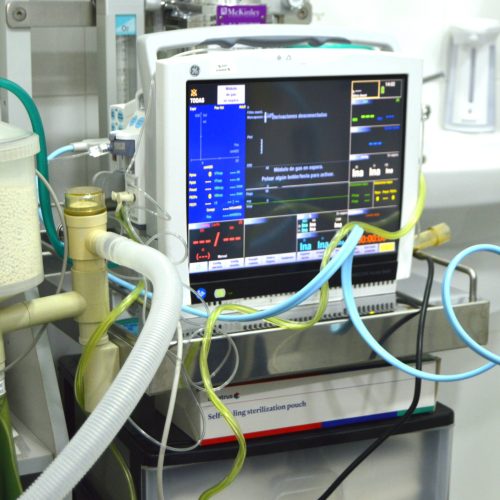

Anestesia y monitorización